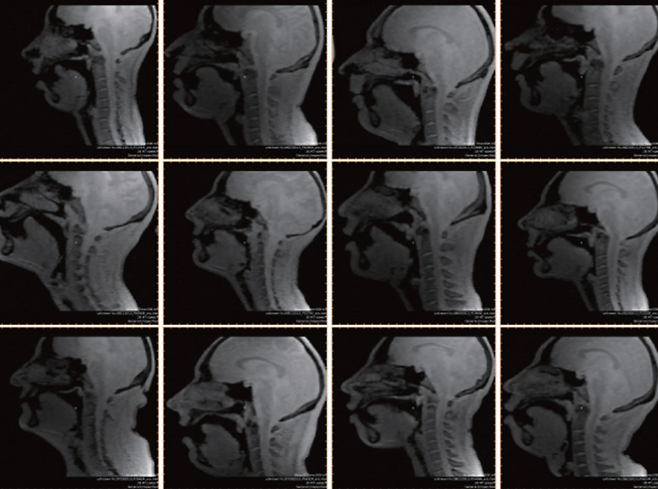

MRI로 혀 움직임 실시간 확인

김 원장은 “그간 근육의 움직임을 확인해 구강 내에서 혀가 어떻게 움직이는지 파악하기 어려웠다”며 “최근 ‘실시간 자기공명영상(real time MRI)’ 기법이 발전하면서 혀의 움직임을 실시간으로 확인할 수 있게 됐다”고 말했다.

실시간 자기공명영상 기법은 MRI를 이용한 인체 촬영 이미지를 영상으로 확보하는 기술이다. 지금까지는 심장의 움직임을 보는 데 주로 활용됐지만, 최근 음향 연구에도 이 기법이 활발하게 쓰이고 있다.

2018년 11월 캐나다 빅토리아에서 열린 제176회 ‘미국음향학회(ASA)’ 연례회의에서 티모시 그리어 서던캘리포니아대 박사과정 연구원은 “비트박스를 하는 사람(비트박서)의 구강 구조를 실시간 자기공명영상 기술로 관측한 결과 소리가 생성될 때 성도 내 공간에서 나타나는 구조적인 변화를 확인하는 데 성공했다”고 발표했다.

가령 비트박서들은 스네어 드럼(뒷면에 쇠 울림줄을 댄 작은 북) 소리를 따라할 때, 방출음을 사용하는 것으로 알려졌다. 방출음은 구강 내 압력을 높인 뒤 공기의 출입을 막은 곳을 열어서 내는 소리다. 그런데 연구팀은 일부 비트박서는 방출음 없이도 스네어 드럼 소리를 재연할 수 있다는 사실을 발견했다.

연구팀은 이런 변화를 분석해 혀와 입천장 등 소리를 만들어내는 데 관여하는 다양한 신체 부위의 움직임을 분석하는 알고리즘을 개발했고, 비트박서를 포함해 다양한 분야에서 전문 음악가의 발성을 조사하는 데도 적용할 수 있다고 밝혔다.

김 원장은 “실시간 MRI 기술이 아직 목소리를 시각화하는 수준은 아니다”라며 “향후 구강 내부의 움직임에 대한 데이터가 계속 축적되면 래퍼가 랩을 하는 동안 자신의 혀의 움직임을 확인하고 실력을 늘리는 데 활용할 수 있을 것”이라고 말했다.